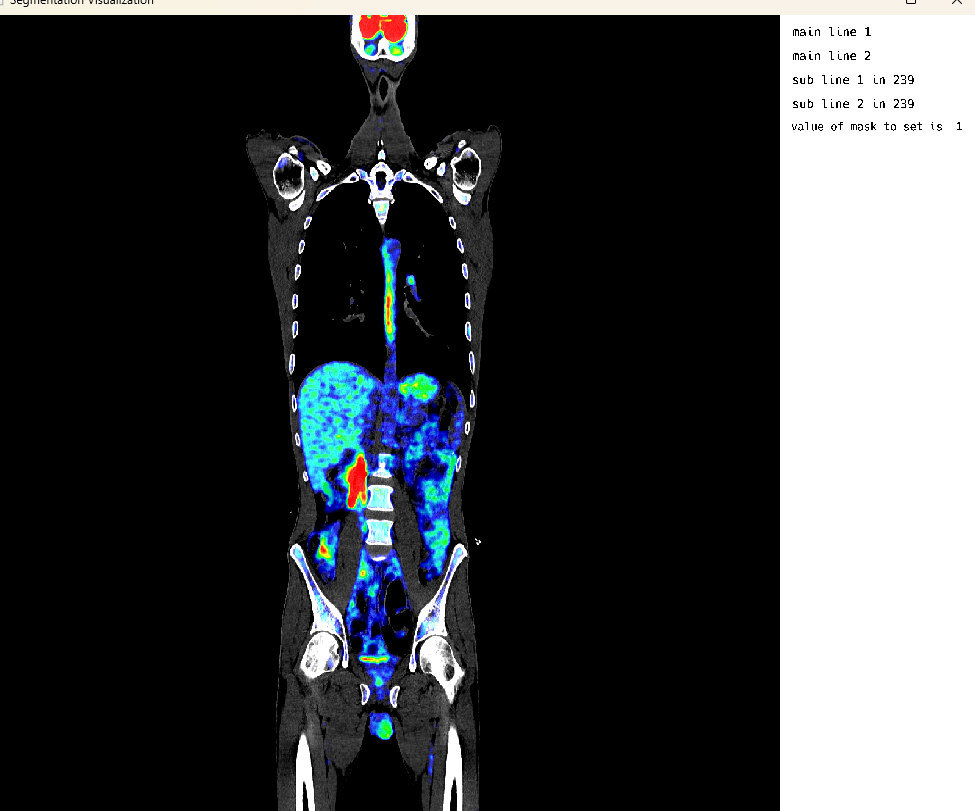

Single Image Mode: Overlaid Studies

This cell demonstrates the visualization of overlaid medical imaging studies. In this example, CT and PET scans of the same patient are loaded and visualized together, allowing for comparison and correlation of different imaging modalities. The ITK-style workflow is used for loading and processing the images.

using MedEye3d

medEyeStruct = MedEye3d.SegmentationDisplay.displayImage(petOverlaidImagesArg)The ITK-style workflow outputs include: - Loading overlaid images using ITK-style workflow - Loading CT: /home/dorachan/Downloads/ct_soft_pat_3_sudy_0.nii.gz - Loading PET: /home/dorachan/Downloads/pet_orig_pat_3_sudy_0.nii.gz - CT size from SITK: (512, 512, 976) - PET size from SITK: (200, 200, 488) - CT spacing from SITK: (0.9765625, 0.9765625, 1.0) - PET spacing from SITK: (4.0728302001953125, 4.0728302001953125, 2.0) - Resampling PET to CT space… - Final CT size: (512, 512, 976) - Final PET size: (512, 512, 976) - Fixed PET texture numb to 3 - Fixed PET range to: Float32[0.13950741, 3457.534]